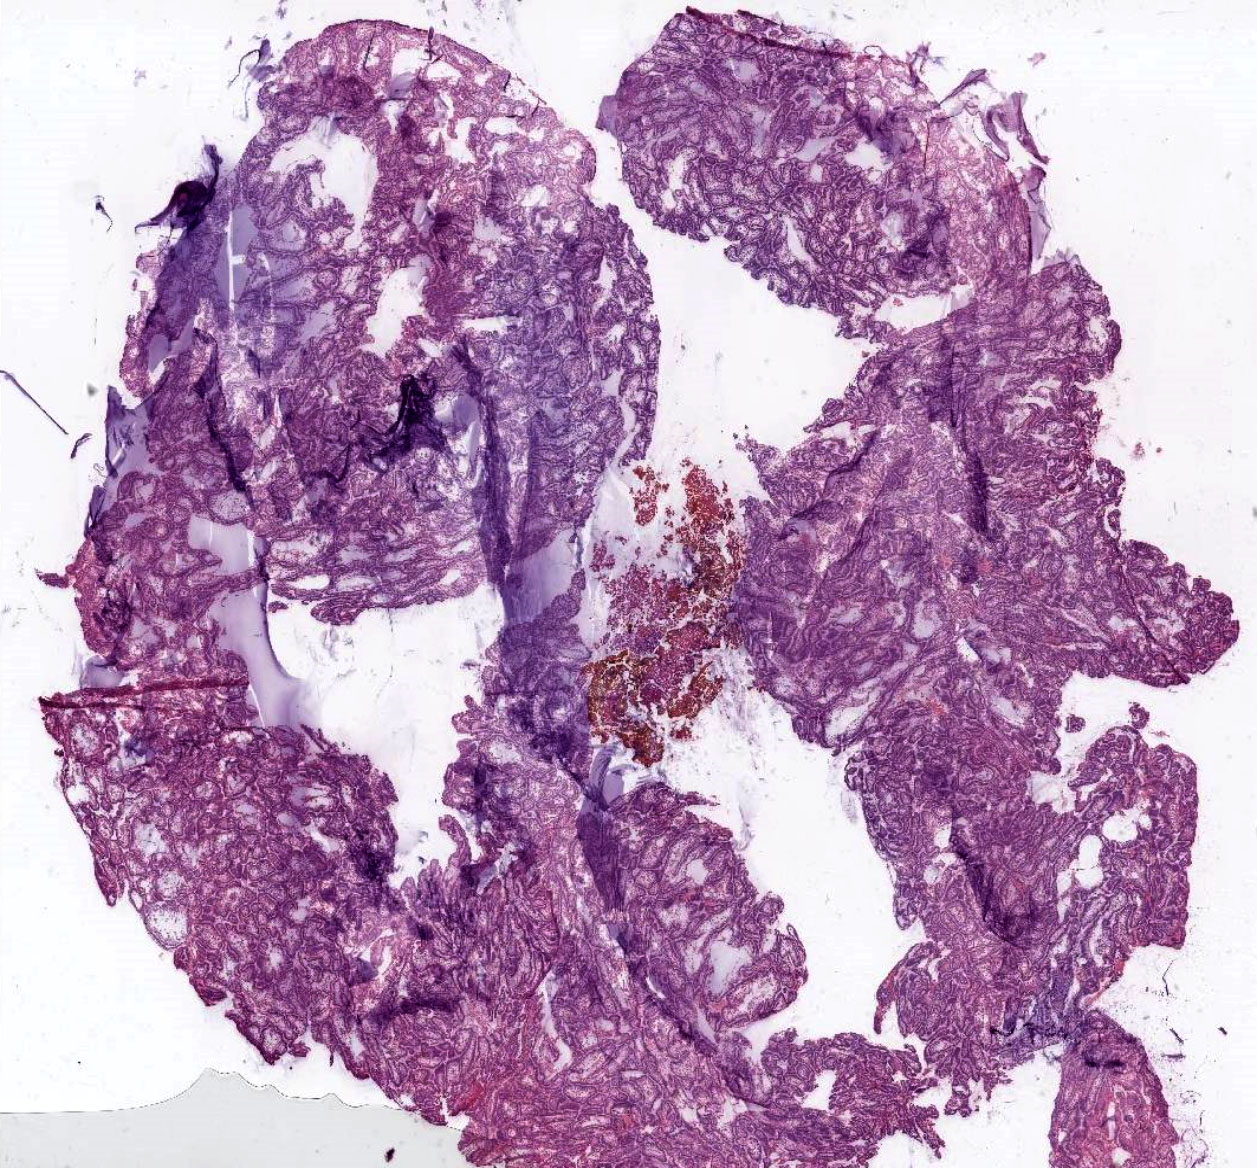

Microscopic (histologic) description

- Within the epithelial islands and cords of conventional ameloblastoma and the cystic epithelial lining of unicystic ameloblastoma, the odontogenic epithelium shows similar changes:

- Columnar cells with hyperchromatic nuclei at basal layer, exhibiting peripheral palisading

- Cells show reverse polarization away from basement membrane (Vickers-Gorlin change)

- Subnuclear vacuolization

- Suprabasal cells with a loose, network-like arrangement, recapitulating stellate reticulum formation seen in normal odontogenesis

- No dentin or enamel formation

- Ameloblastoma, conventional type may show macrocystic change of the tumor islands; when a limited portion of this phenomenon is sampled at initial biopsy, the appearance may suggest an odontogenic cyst, NOS or ameloblastoma, unicystic type

- Rarely, involvement of the inferior alveolar nerve has been reported in benign, conventional ameloblastoma (Oral Surg Oral Med Oral Pathol Oral Radiol Endod 2001;91:557, Br J Oral Maxillofac Surg 2013;51:757)

- Ameloblastoma, conventional type has at least 6 histopathological patterns

- Single patterns may predominate within a given lesion, often mixed with 1 or more patterns

- Microscopic pattern has no documented prognostic significance

- Follicular: most common subtype; islands of odontogenic epithelium in fibrous connective tissue; may be cystic; classic peripheral palisading and stellate reticulum-like areas

- Plexiform: cords and sheets of anastomosing odontogenic epithelial cells; classic peripheral palisading and reverse polarity not always obvious

- Acanthomatous: squamous metaplasia and variable keratinization of stellate reticulum-like cells

- Granular cell: stellate reticulum-like cells have granular eosinophilic cytoplasm; less commonly involves cells at periphery of nests

- Basal cell / basaloid: least common histologic subtype; islands of hyperchromatic basal cells without stellate reticulum-like areas

- Desmoplastic: compressed and angular islands of epithelial tumor cells with dense moderately cellular fibrous connective tissue or collagenous stroma; the formation of metaplastic bone trabeculae is also described

- Ameloblastoma, unicystic type has 3 histopathological patterns

- Single cystic lesion lined by ameloblastic epithelium that shows typical features of ameloblastoma in some areas, including columnar basal cells in palisading arrangement with vacuolated cytoplasm, hyperchromatic nuclei polarized away from basement membrane

- Suprabasal cells loosely textured and noncohesive resembling stellate reticulum, epithelial invagination, epithelial edema and separation

- Microscopic variants (may result in treatment differences - controversial)

- Luminal: cystic odontgenic epithelium with characteristic features (above) lining fibrous connective tissue wall

- Intraluminal: cystic odontgenic epithelium with characteristic features (above) lining fibrous connective tissue wall, with tumor extending into the cystic luminal space; may have intraluminal plexiform patterns

- Mural: cystic odontgenic epithelium with characteristic features (above) lining fibrous connective tissue wall but with the additional finding of definite ameloblastoma tumor islands within the fibrous connective tissue wall

Microscopic (histologic) images

Contributed by Kelly Magliocca, D.D.S., M.P.H. and Anne C. McLean-Holden, D.M.D., M.S.